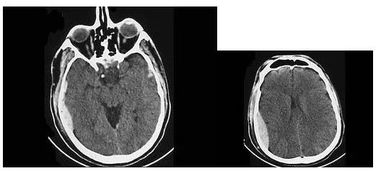

1. 更高的图像分辨率:CT可以提供横断面图像,图像分辨率高,可以清晰地显示组织结构和器官的细节,有助于更准确地诊断疾病。

CT扫描通过精确的X射线束对人体进行扫描,能够获得高清晰度、高分辨率的图像。这些图像可以清晰地显示人体内部的器官和组织结构,对于诊断疾病具有重要意义。与X光相比,CT图像的分辨率更高,能够更准确地识别病变。